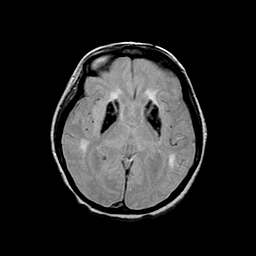

Basal Ganglia Calcification: proton density-weighted MR -- Slice #9

[Home][Help][Clinical] Slice 9